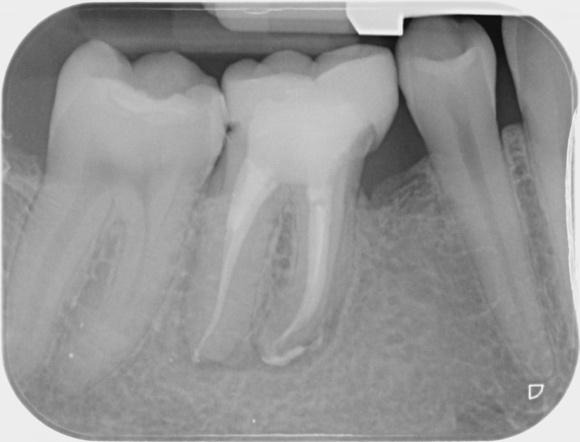

Immediate post-op and 18-month review IOPA

Displaying nice healing and a marked reduction in the PARL. RD sent review x-ray mentioning marginal gap at distal crown margin which ideally needs rectifying to maintain an optimal coronal seal on the root treatment!